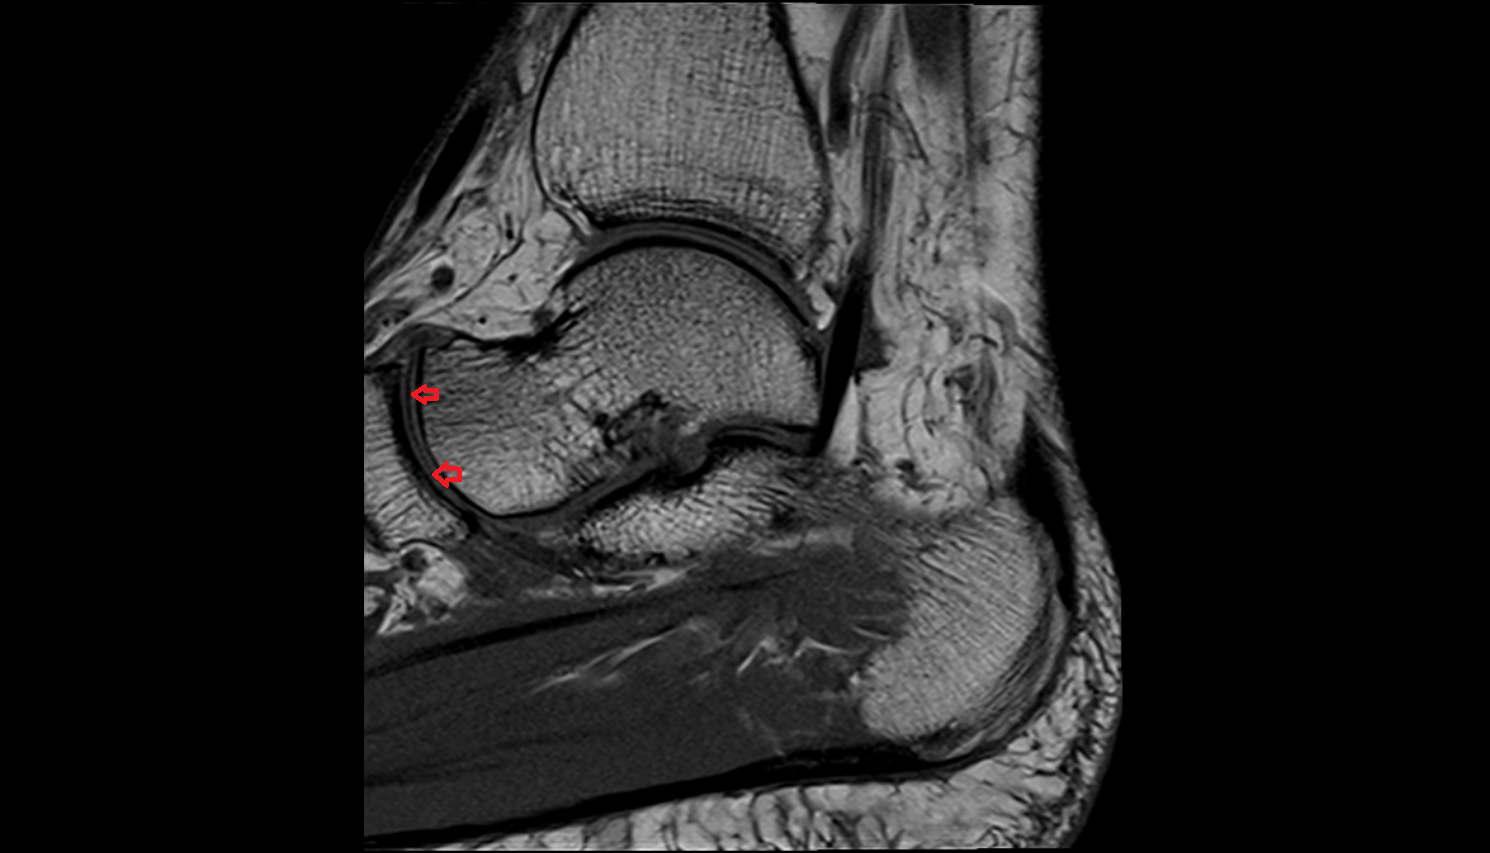

- Ankle joint

- Talus

- Calcaneus

- Anterior talofibular ligament

- Posterior talofibular ligament

- Deltoid ligament complex